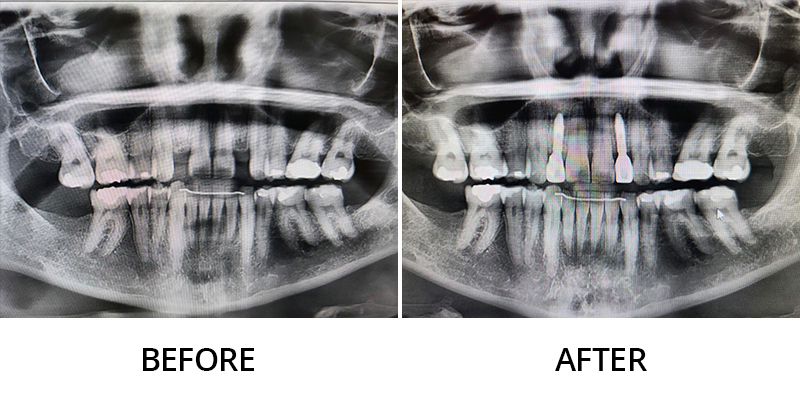

We invite you to explore this smile gallery page to see some of the beautiful results Dr. Kevin Grimm has helped his patients achieve. If you have questions about our dental services, or to schedule your personal consultation with our skilled dentist in Okemos, Michigan, please contact Okemos Smile Center today at (517) 349-3110. We look forward to helping you transform your smile!